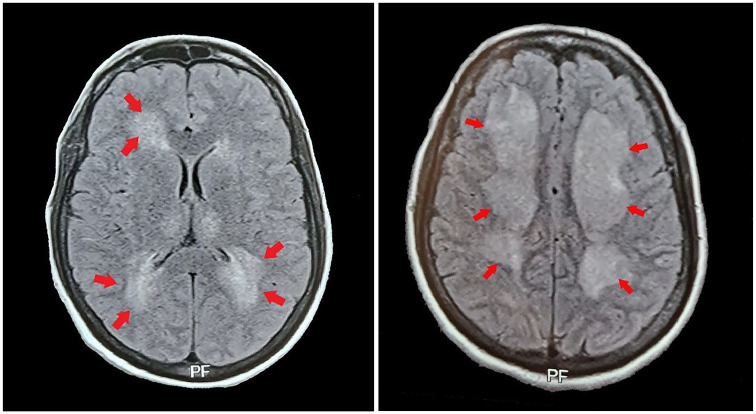

Dengue virus infection is a significant public health concern, particularly in endemic areas. This case report highlights the difficulties in diagnosing expanded dengue syndrome (EDS) in a dengue-endemic region. This case report emphasizes keeping high suspicion of index for (EDS) among patients presenting with fever and neurological manifestations particularly in regions where dengue is endemic. The atypical neurological symptoms and inconclusive initial investigations underscore the diagnostic challenges associated with (EDS). Prompt recognition and appropriate laboratory testing, such as detecting dengue NS1 antigen, can aid in accurate diagnosis and subsequent management of patients with this condition. Increased awareness among healthcare providers in endemic regions is crucial for timely identification and intervention in case of dengue-associated neurological complications. Therefore, a multidisciplinary approach is required for time-effective management.